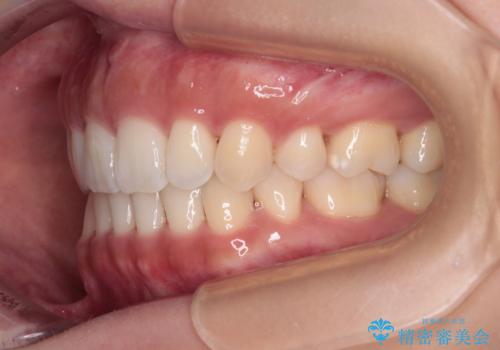

- 上下前歯の隙間と口元の出っ張った感じを気にして来院された患者様です。

上下の隙間は舌突出癖によるもので、またその癖により前歯が前方に出ている状態でした。

口元の出っ張りを改善するため、上下左右第一小臼歯4本を抜去し、ワイヤー装置にて矯正治療を行うこととしました。

舌の突出癖を改善するためのトレーニングをしっかりと行っていただいたことで、比較的スムーズに治療を進めることができました。

口元の突出感もしっかりと改善することができました。